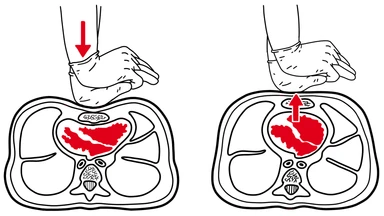

Cardiopulmonary resuscitation – CPR, for short – is a game-changer when a person's heart has stopped beating. Despite its effectiveness, the technique itself is relatively simple.